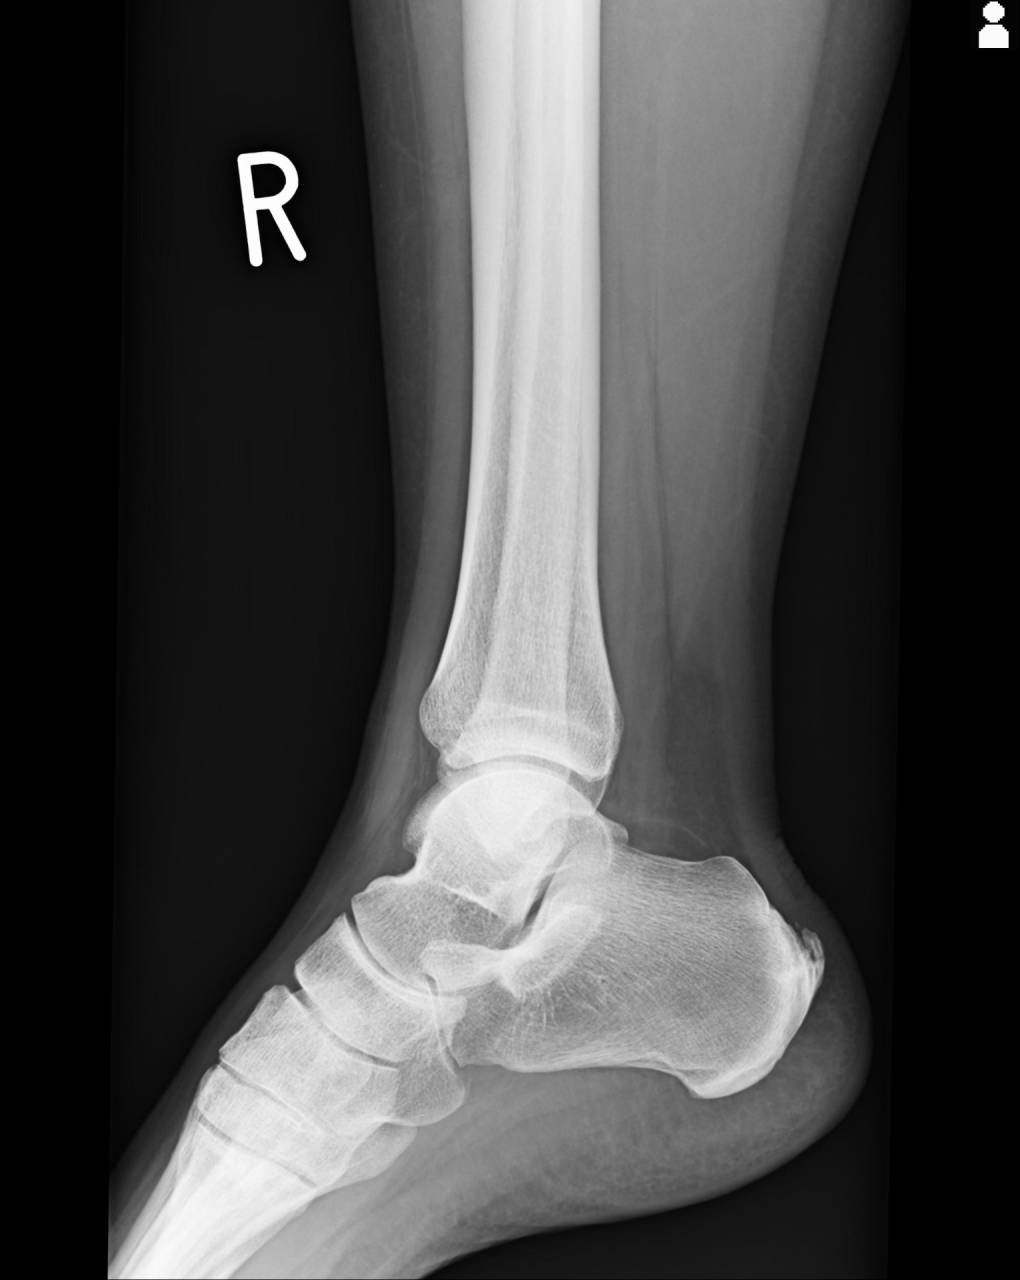

40代女性、ゴルフのプレー中に歩いていて右足を捻り怪我をしたとのこと。

翌日に自宅近所の整形外科に行きレントゲン検査等で診てもらったとのこと。

判定は捻挫と言われたとのことで、「1週間しても痛みが引かなかったら別の原因がある」と言われ、5日程生活していて痛みがまったく引かないとのことで当整骨院に来院されました。

検査を行っていくと、右足外観は腫脹が足関節周囲、足の甲にあり、皮下出血は薄く出ている状態でした。

右足関節の関節可動域を診ていくと健側の左と比較すると底屈は-10度、背屈は-15度で足関節の可動域に制限がある状態で、その後検査を行っていくと距骨の亜脱臼があり、足関節の可動域制限と特有の腫脹が出ていると判定しました。

圧痛を確認していくと、右腓骨部(腓骨遠位)と二分靭帯の部分特に立方骨側にあり、腫脹が強く出ている部分と一致します。

超音波観察装置(エコー)にて画像検査を行っていくと、圧痛があった腓骨、立方骨に骨折の徴候が診られたので、当整骨院が提携している病院にてレントゲン検査の依頼をしました。

撮影したレントゲン画像を確認していくと、エコーで検査して骨折が怪しかった部位と同じ部位に骨折が判明し、骨折として施術を進めていきます。